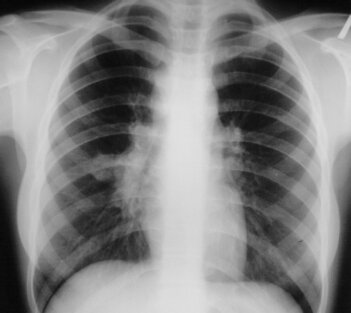

2. Чем КТ отличается от рентгенографии?

КТ это послойное сканирование. При традиционном КТ кольцо сканера делает полный круг, затем стол смещается на заданное расстояние(шаг сканирования), делается следующий "срез". А вот на рентгенограмме изображения органов наслаиваются друг на друга, что мешает их рассмотреть и выявить изменения. Томограмма состоит из нескольких «срезов», что значительно повышает информативность снимков. Чем меньше шаг сканирования, тем лучше видна структура органов, их расположение.